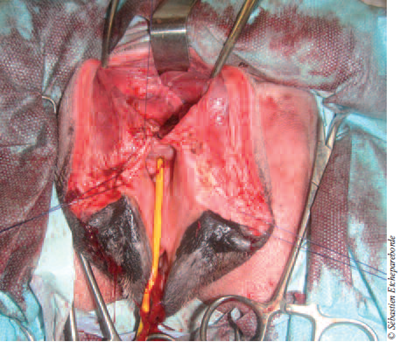

photo 1

Photo 1 – Coupe transversale au scanner de la masse juste en arrière du bassin. Ventralement à la masse, on aperçoit un petit point noir qu’il est l’urètre.

Une sonde urinaire avait été mise en place préalablement pour repérer l’urètre au scanner. La masse mesurait 10 cm de long sur un diamètre d’environ 5 cm. Aucune des structures environnantes ne semblaient envahies par la masse.